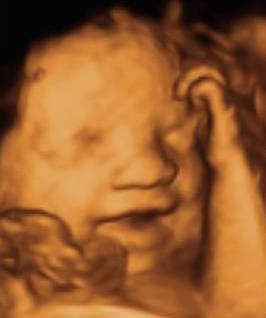

Echographie obstétricale

La surveillance d’une grossesse normale nécessite la pratique de 3 examens échographiques à 12 semaines, 22 semaines et 32 semaines d’aménorrhée en plus de la surveillance mensuelle par votre médecin.

C’est une technique qui utilise les ultrasons. Dans les conditions d’utilisation médicale aucun risque n’est connu. L’échographie Doppler repose sur le même principe. On analyse la circulation sanguine fœtale, placentaire et de l’utérus maternel afin d’évaluer la qualité des échanges materno-fœtaux et le bien être fœtal.